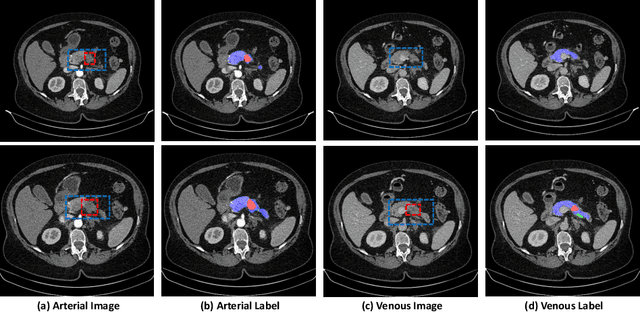

Abstract:Pancreatic ductal adenocarcinoma (PDAC) is one of the most lethal cancers among population. Screening for PDACs in dynamic contrast-enhanced CT is beneficial for early diagnose. In this paper, we investigate the problem of automated detecting PDACs in multi-phase (arterial and venous) CT scans. Multiple phases provide more information than single phase, but they are unaligned and inhomogeneous in texture, making it difficult to combine cross-phase information seamlessly. We study multiple phase alignment strategies, i.e., early alignment (image registration), late alignment (high-level feature registration) and slow alignment (multi-level feature registration), and suggest an ensemble of all these alignments as a promising way to boost the performance of PDAC detection. We provide an extensive empirical evaluation on two PDAC datasets and show that the proposed alignment ensemble significantly outperforms previous state-of-the-art approaches, illustrating strong potential for clinical use.

Abstract:Integrating multi-phase information is an effective way of boosting visual recognition. In this paper, we investigate this problem from the perspective of medical imaging analysis, in which two phases in CT scans known as arterial and venous are combined towards higher segmentation accuracy. To this end, we propose Phase Collaborative Network (PCN), an end-to-end network which contains both generative and discriminative modules to formulate phase-to-phase relations and data-to-label relations, respectively. Experiments are performed on several CT image segmentation datasets. PCN achieves superior performance with either two phases or only one phase available. Moreover, we empirically verify that the accuracy gain comes from the collaboration between phases.